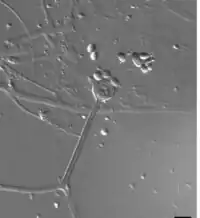

Apophysomyces variabilis resembles the other three members of the genus Apophysomyces but is characterized by the variable appearance of its sporangiospores and sporangiophores which range from club-shaped to trapezoidal to flattened spheres. The sporangiophore can measure up to 400 μm in length and has a funnel-shaped apophysis or swelling below the columella. Hyphae are smooth-walled, aseptate, and branched.[4]

Unlike most members of the Mucorales, Apophysomyces species often fail to sporulate under standard clinical laboratory culture conditions. These fungi require Czapek's agar (CZA), a nutrient-defined medium.[2] Colonies grow rapidly at 37 °C on CZA and initially appear white and woolly becoming greyish brown with age.[4][6][7] Colonies are grey and floccose, will grow on the lid of the petri dish, and are colourless on reverse.[8] Sporangiosphores are unbranched, smooth-walled, and light brown.[4] Sporangia are apophyseal, pyriform, beginning as whitish and turning brown with maturity. Sporangiospores are variable in size and shape.[6] Sexuality has not been observed in A. variabilis.[8]